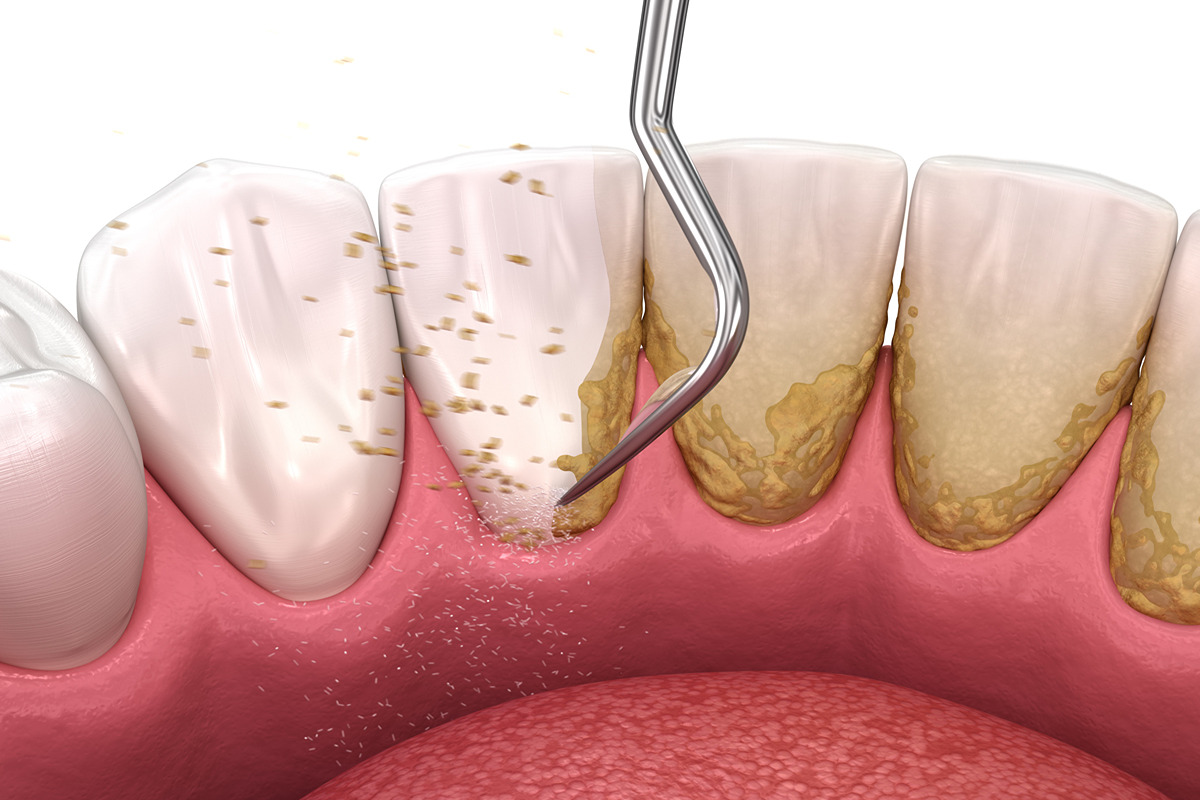

۲- جرمگیری مکانیکی

در این مرحله با استفاده از دستگاه اولتراسونیک مخصوص جرم بالای لثه پاکسازی میشود. نوک دستگاه دارای سریهای تفلونی یا پلاستیکی است تا سطح کامپوزیت آسیب نبیند.

۳- جرمگیری دستی

برای نقاط حساس یا بخشهای بین دندانی، از ابزار دستی بسیار ظریف استفاده میشود. در این مرحله دندانپزشک فشار کمی وارد میکند تا سطح کامپوزیت خراشیده نشود.